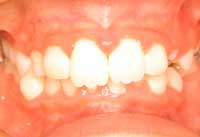

時々、保健センターの1歳半児検診で、虫歯を見て「これは形成不全」といわれ、直す必要はないですよ、といわれる患者さんがいるようです。「形成不全症」というのは遺伝性の病気で、エナメル質、または象牙質の元となる細胞がうまく作られなかったものです。お口中の全部の歯が茶色っぽくなったり白っぽくなったりします(右上下写真)。